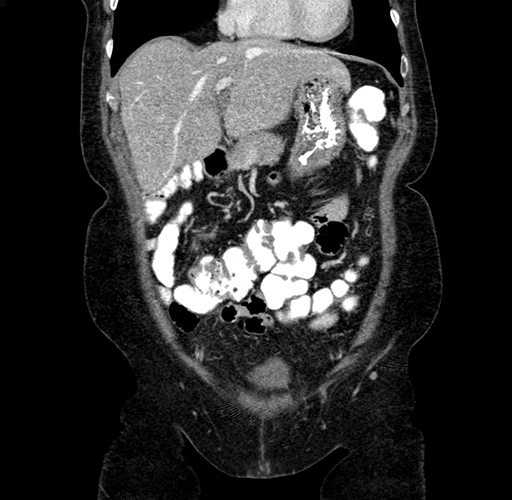

Pre-Chemo: Coronal Venous

Coronal Venous